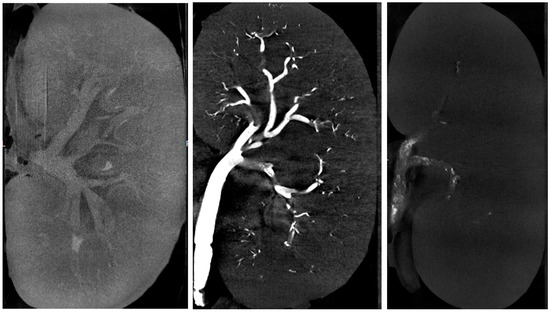

2.2. Micro-Computed Tomography

3.1. Micro-Computed Tomography Parameters

3.1.1. Objectively Assessed µCT Parameters